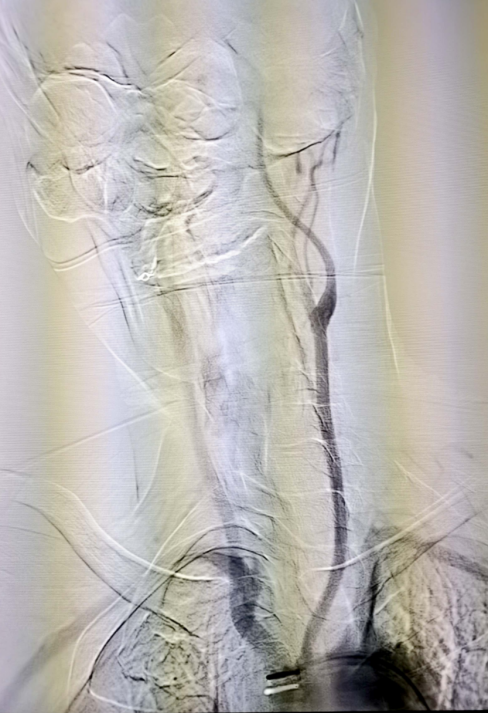

弓上脑血管造影